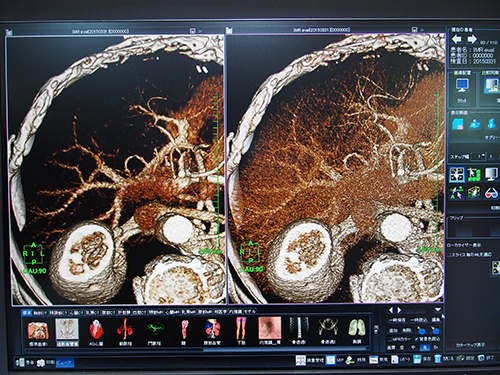

統計的CT画像ノイズ低減機能(W.I.P.)は,thin sliceのボリュームデータに適応した画像ノイズ低減機能。各ピクセルの三次元的近傍から推定されたノイズの統計量を基にノイズパターンを解析し,元の画像からノイズを差分することで画像ノイズの低減を行う。レトロスペクティブにノイズを低減できるため,thin slice画像再構成などの場合に生じる線量不足による画像ノイズを低減することができる。画像ノイズ(SD)測定では,線量を約1/4に低減しても同等の画質を得られるという。ノイズを低減することでコントラストが向上し,物体抽出の精度が上がるため,MIP画像やVR画像などで血管をより明瞭に描出することが可能になる。ワークステーションによる画像解析の精度は元画像のクオリティに依存するため,ノイズの少ない画像を得られることで,画像解析も容易になる。

レトロスペクティブにノイズを低減する統計的CT画像ノイズ低減機能(W.I.P.)

ノイズに埋もれた血管もノイズを低減することで観察可能

VR表示など,さまざまな表示法でノイズ低減効果が実感できる。